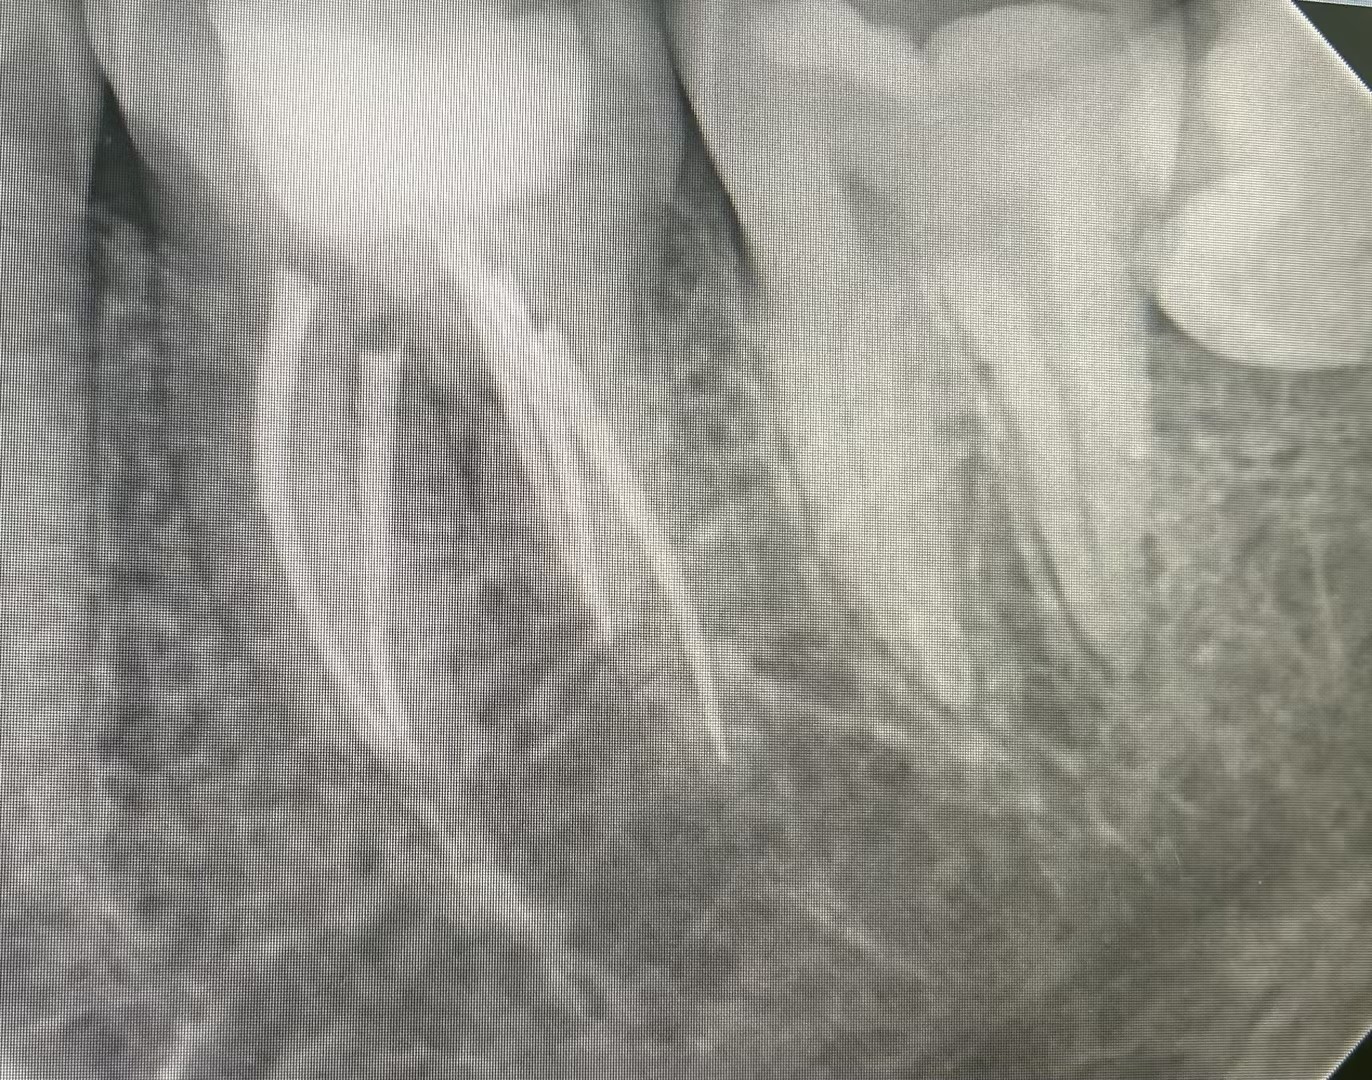

患者因左下后牙反复疼痛就诊,牙体牙髓病2科医生接诊后,通过详细口腔检查及口腔CBCT影像评估发现,疼痛根源为36慢性牙髓炎,且该牙齿解剖结构特殊——远中颊根存在双根管形态。据了解,下颌第一磨牙本身位置靠后、视野受限,治疗操作难度较大,而远中颊根双根管的解剖变异进一步增加了治疗复杂度,对医生的操作精度和根管系统解剖认知提出极高要求。

诊疗过程中,医生凭借对牙齿解剖结构的深刻掌握,结合根管显微镜的精准视野,仔细探查根管口、疏通根管通路,成功定位并清理两条细小根管内的感染组织。随后对根管进行严密充填,确保根管系统完全封闭,有效防止再次感染。整个治疗过程规范有序,患者术中感受良好,术后疼痛症状明显缓解,恢复效果理想。